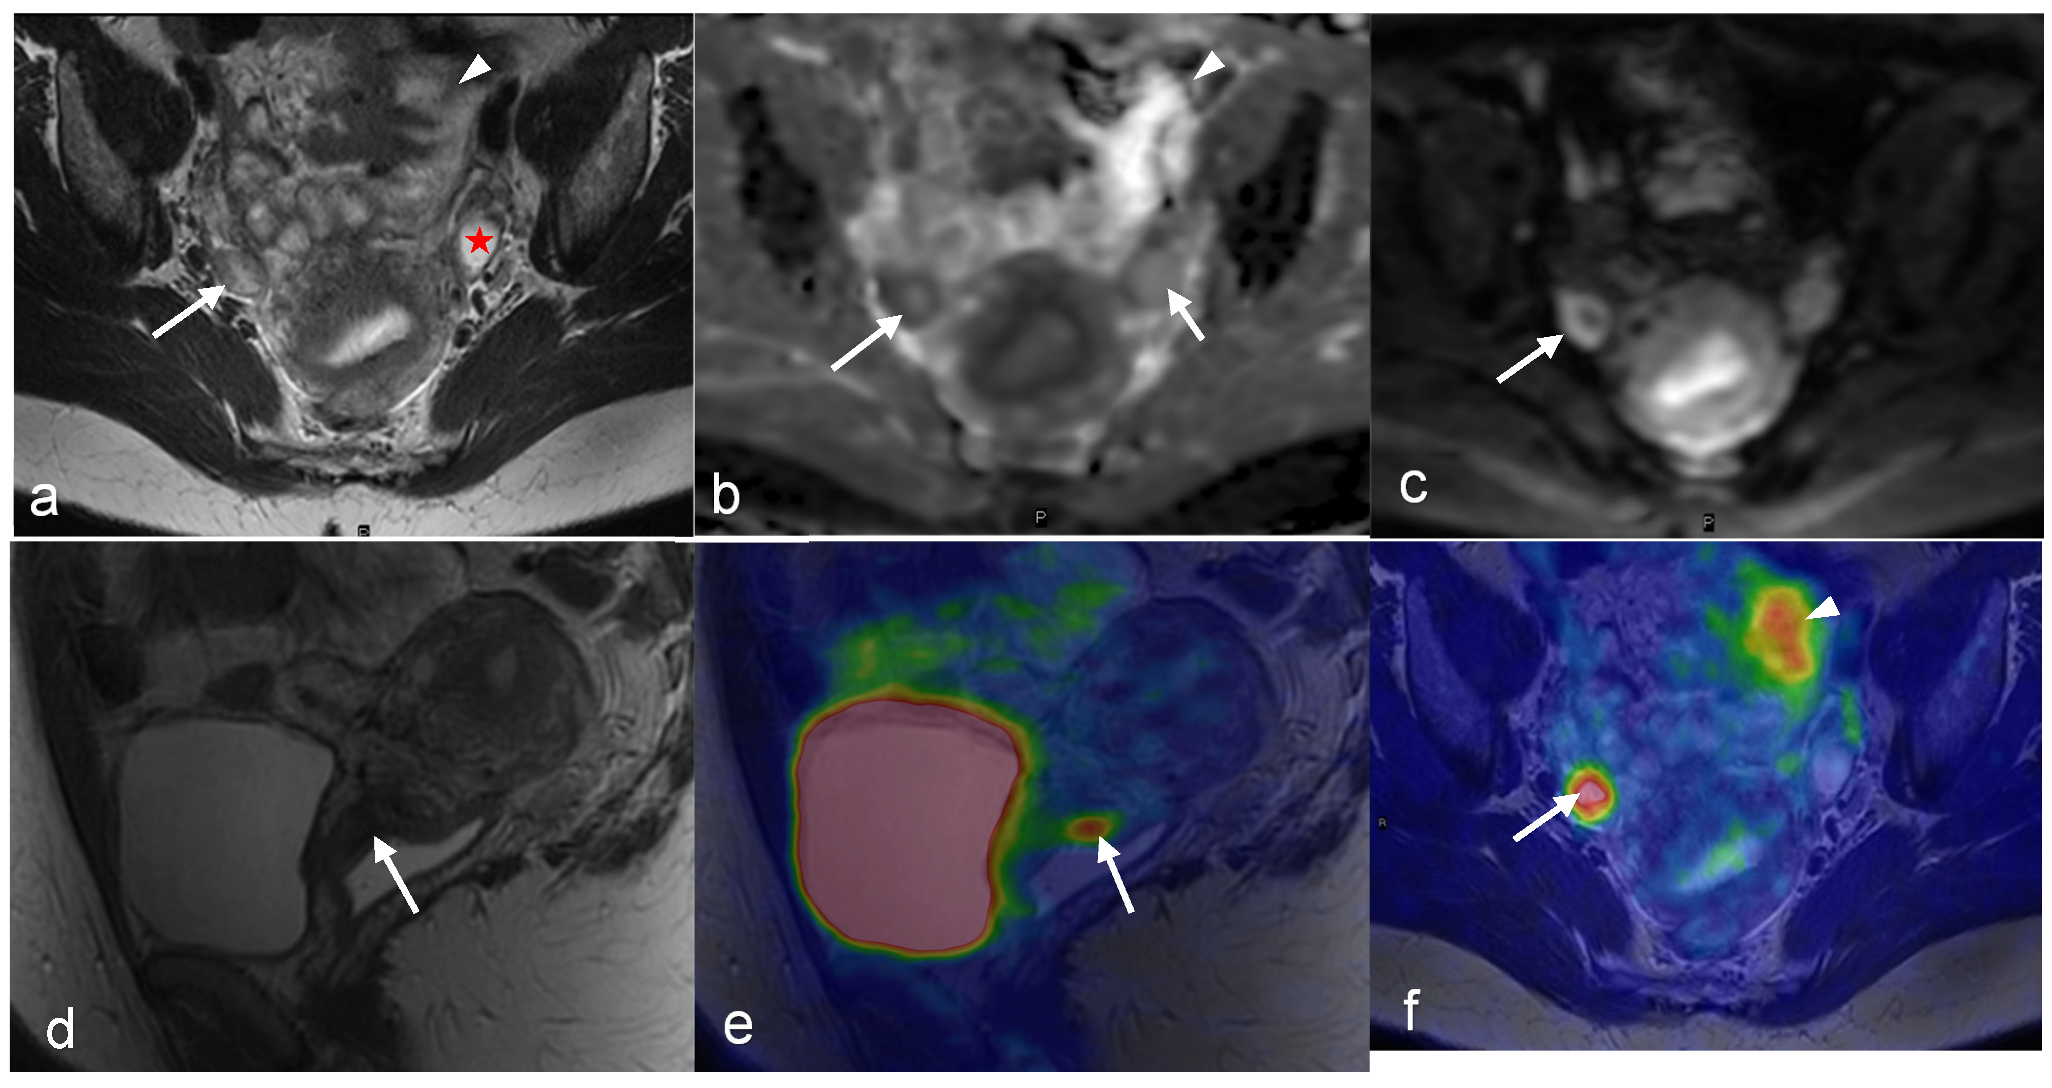

- Tsuyoshi, H.; Tsujikawa, T.; Yamada, S.; Chino, Y.; Shinagawa, A.; Kurokawa, T.; Okazawa, H.; Yoshida, Y. FDG-PET/MRI with high-resolution DWI characterises the distinct phenotypes of endometrial cancer. Clin. Radiol. 2020, 75, 209–215. [Google Scholar] [CrossRef] [PubMed]

- Tsuyoshi, H.; Tsujikawa, T.; Yamada, S.; Okazawa, H.; Yoshida, Y. Diagnostic value of 18F-FDG PET/MRI for staging in patients with endometrial cancer. Cancer Imaging 2020, 20, 75. [Google Scholar] [CrossRef]

- Ironi, G.; Mapelli, P.; Bergamini, A.; Fallanca, F.; Candotti, G.; Gnasso, C.; Taccagni, G.L.; Sant’Angelo, M.; Scifo, P.; Bezzi, C.; et al. Hybrid PET/MRI in Staging Endometrial Cancer: Diagnostic and Predictive Value in a Prospective Cohort. Clin. Nucl. Med. 2022, 47, e221–e229. [Google Scholar] [CrossRef]